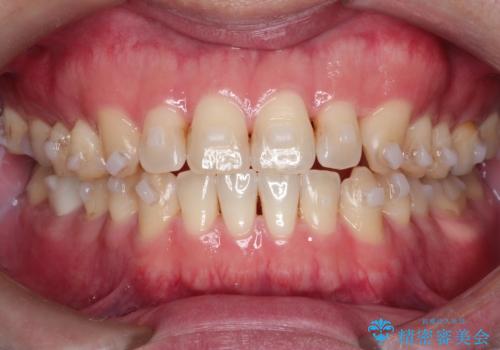

マウスピース矯正で自然な笑顔を実現! 前歯の咬み合わせを治しました。

- 前歯の咬み合わせが気になるとのことで来院されました。

前歯が噛んでいない状態(開咬)のため、インビザライン矯正で改善することとしました。